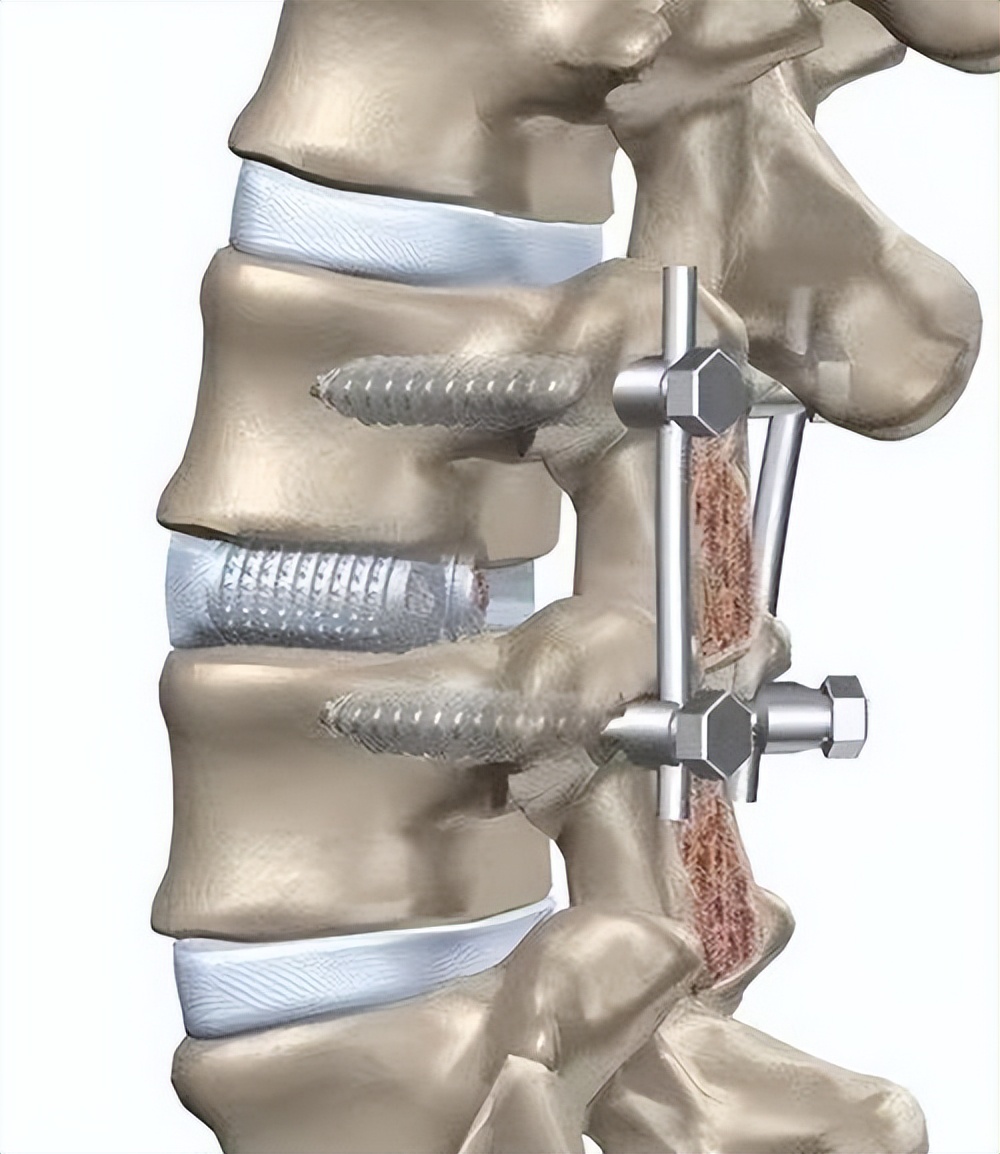

医学影像 原来腰椎钢钉是这样连接的